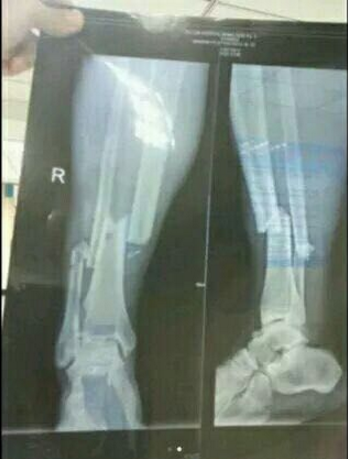

| Subject | (혐) 뎀바바 부상 장면 |

8개월 부상에 시즌아웃이라는데..장난 아니네요.. 0